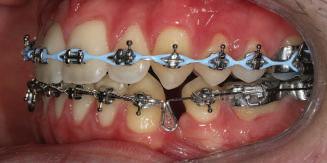

20 Dental Tribune Bulgarian Edition / октомври 2022 г. П ациентите със завършен растеж и скелетни проблеми обикновено представляват предизвикателство за ортодонт ската практика. Необходимостта от изваждане на зъби в комбинация с особеностите на възрастовата ортодонтия изисква особено внима ние. Фокусът върху критично важното значение на позицията на долните резци във връзка с дългосроч ната стабилност и постигането на оптимални оклузални взаимоотношения при затварянето на екстракционните пространства лесно може да излезе извън контрол. Когато към тези чисто кли нични проблеми се добави и стресът от натоваре ната практика, предизвикателството става още по-голямо. Всички тези фактори налагат използ ването на доказан подход с ясни и последовател ни стъпки, в което се разкрива силата на дисциплината „Алекзандър“ – предвидим протокол през целия процес на елиминиране на ротациите, ниве лиране на дъгите, затваряне на екстракционните пространства и финализиране на случая. Именно такъв е и случаят, който презентираме –екстракционен, скелетен клас 3 при възрастен па циент, лекуван по системата „Алекзандър“. ПРЕДВИДИМИ РЕЗУЛТАТИ ПРИ ПАЦИЕНТИ СЪС ЗАВЪРШЕН РАСТЕЖ И СКЕЛЕТЕН КЛАС 3, ИЗПОЛЗВАЙКИ ЕКСТРАКЦИОННО ЛЕЧЕНИЕ ПО ДИСЦИПЛИНАТА „АЛЕКЗАНДЪР“ Д-р Радой Димитров, България Преди започване на лечение клиничен случай | ортодонтия Фиг. 1а–1e Преди започване на лечение. Пациентът пристига в практиката с основното оплакване от невъзмож ност за нормално дъвчене. Снета е цялата необходима диагностична ин формация. Фиг. 1f–1h Снимки в профил и анфас. Фиг. 1i–1k Панорамна снимка, телерентгенография и анализ на телерент генография. Фиг. 1а Фиг. 1d Фиг. 1f Фиг. 1g Фиг. 1h Фиг. 1e Фиг. 1b Фиг. 1c Фиг. 1i Фиг. 1j Фиг. 1k

closed.

21Dental Tribune Bulgarian Edition / октомври 2022 г. ДИАГНОСТИЧНИ РЕЗУЛТАТИ: 1. Възраст на пациента: 21 години 2. Скелетен клас III (ANB 0) 3. Зъбен клас 3 4. Ръбцова захапка във фронта, кръстосана в дисталните участъци 5. Тясна горна челюст 6. Overjet – 0 мм, Overbite – 0 мм 7. Несъответствие на горната с долната средна линия 8. Единични контакти в ЦО 9. Хиподивергентен тип на растеж SN/MP – 33.5 10. Неравен гингивален контур 11. Неравна линия на усмивката 12. Тенденция за рецесии в долен фронт ПРЕПОРЪЧИТЕЛНО ЛЕЧЕНИЕ: Пълно ортодонтско лечение с метални брекети „Алекзандър“ Корекция на клас 3 захапката в областта на кучешките зъби с екстракция на първите пре молари в долна челюст Корекция на кръстосаната захапка в дистални участъци Коригиране на ръбцовата захапка във фронта Подобряване на ОJ и OB на пациента Стрипинг в долен фронт Подреждане на зъбите в горната и долната челюст Професионално хигиенизиране и профилактични дентални прегледи са препоръчителни на всеки 6 месеца. 1-ви месец След 1 месец са залепени брекети в горната челюст – поставена е еластична дъга. 016 NiTi. В долната челюст са елиминирани ротациите, поставена е стоманена дъга. 016SS, закалена с ток, и еластична верижка за затваряне на пространствата. 3-ти месец В долната челюст е поставена трета дъга – 17 x 25 NiTi с къси лигатури и верижка

В горната челюст се затварят пространствата с дъга .016SS и верижка. 5-и месец На 5-ия месец след залепяне на брекетите в долната челюст е поставена стоманена дъга 16 x 22 SS с четвъртито сечение, омега луп и тай бек. В горната челюст е поставена дъга 17 x 25 NiTi. Поради липсата на стабилни оклузални контакти са поставени лингвални верижки в областта на моларите, за да се предотврати нежелана ротация на 7-ите зъби. 6-и месец На 6-ия месец от началото на лечението са екстрахирани долните първи премолари, поставена е дъга 16 x 22 SS със затваряща чупка teardrop. Чупката се активира всеки месец по 1 мм с чинч-бек. клиничен случай | ортодонтия СТЪПКИ НА ЛЕЧЕНИЕТО Начало на лечението Лечението започва с поставяне на апарат за бърза експанзия в горната челюст. През първия месец от лечението са направени 24 оборота на апарата за експанзия. Залепени са брекети в долната челюст, поставена е дъга 17x25 CuNiTi, като са предпи сани клас 3 ластици (1/4”,4 1/2 oz) по време на сън, за да се осигури контрол върху торка на долните резци. Фиг. 2а Фиг. 3a Фиг. 4a Фиг. 3b Фиг. 4b Фиг. 3c Фиг. 4c Фиг. 3d Фиг. 4d Фиг. 3e Фиг. 4e Фиг. 5a Фиг. 5b Фиг. 5c Фиг. 5d Фиг. 5e Фиг. 6a Фиг. 6b Фиг. 6c Фиг. 6d Фиг. 6e Фиг. 7a Фиг. 7b Фиг. 7c Фиг. 7d Фиг. 7e Фиг. 2b Фиг. 2c Фиг. 2d